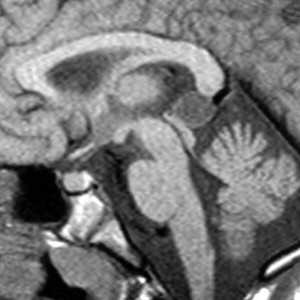

МРТ головного мозга. Т1-взвешенная сагиттальная МРТ. Пинеальная киста.

Пинеальная киста расположена в проекции шишковидной железы. Встречается с частотой 4-11%. Размеры обычно не превышают 1 см, но изредка встречаются больших размеров. В таких случаях она вызывает окклюзионную гидроцефалию. При МРТ головного мозга она имеет все признаки кисты с примесью белка в жидкости, то есть немного светлая на Т1-зависимых МРТ. Изредка встречается геморрагическое содержимое. Киста может по усиливаться периферии при МРТ головного мозга с контрастированием.

МРТ головного мозга. Т1-взвешенная сагиттальная МРТ. Киста кармана Ратке.

Киста кармана Ратке представляет собой редко встречающееся образование из остатков эмбриональной эктодермы (щель Ратке), расположенное между долями гипофиза. Выявляется в любом возрасте, но чаще в 50-60 лет. Клинические проявления связаны с масс-эффектом. При МРТ головного мозга выявляется небольшая (3-5мм) киста с четким контуром, без отека вокруг, однородная по структуре. Сигнал на МРТ головного мозга зависит от содержимого. При серозном содержимом сигнал типично жидкостный, при мукоидном киста светлая на Т1-взвешенных МРТ головного мозга. В 70-80% случаев внутри кисты выявляется неконирастирующийся узелок («пятно») - признак патогномоничный для кисты кармана Ратке. В редких случаях киста достигает больших размеров и даже выходит за пределы седла. Стенка кисты иногда усиливается при МРТ головного мозга с контрастированием. Дифференциальная диагностика при МРТ головного мозга должна проводиться с арахноидадьной и эпидермоидной кистами, тератомой, кистозной аденомой гипофиза и краниофарингиомой. Иногда при МРТ головного мозга киста кармана Ратке напоминает “пустое” турецкое седло. При маленьких размерах кисты ее на до дифференцировать на МРТ с микроаденомой гипофиза.